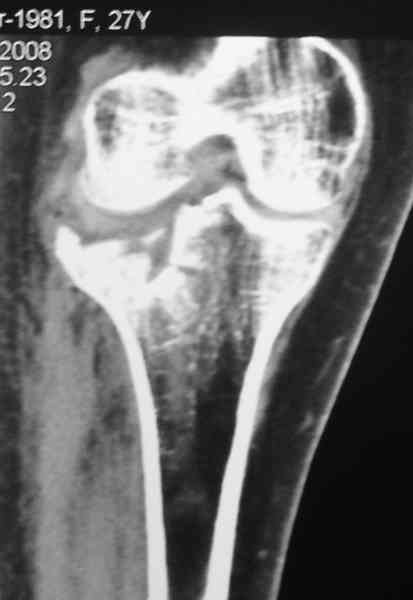

Есть ли возможность сделать КТ?

К большому сожалению КТ пока на ремонте, как запустять, сразу сделаю. Спасибо.

Уважаемый Абдурашид. Если нет противопоказаний , то из оперативных способов, я бы рекомендовал следующие: Полное замещение наружного мыщелка аллотрансплантатом либо открытая репозиция с элевацией и замещение дефекта ауто или аллокостью. В Ваших условиях , я бы рекомендовал второй способ. Во-время элевации необходимо разъединить фрагменты со стороны сустава ( надсечь скальпелем по линиям перелома, а затем тонким остеотомом их разъединить. При помощи долота произвести неполную остеотомию ( захватите не менее 1,5 - 2 см губчатой кости и поднять фрагменты, визуально отрепонировать и фиксировать 2-3 спицами. Дефект заместить костным ауто или аллатрансплантатом. Окончательная стабилизация пластиной ( лучше с угловой стабильностью, либо АВФ - позволит спокойно устранить угловую деформацию.

Недавно поступила больная через 1,5- 2 месяца.

Я согласен с мнением доктора Соломина, что необходимо выполнить СТ. Это поможет Вам не только определить степень повреждения твёрдых тканей, но и увадеть степень сращения. Без СТ не возможно планировать дальнейшую тактику лечения.

У пациента основной проблемой является импрессионый перелом наружного мыщелка, уже неправильно сросшийся, по-видимому. Аппаратом закрыто можно только подправить угол на уровне метадиафиза. Что

улучшит разве что внешний вид конечности, но не решит основной проблемы - грубой деформации суставной поверхности.